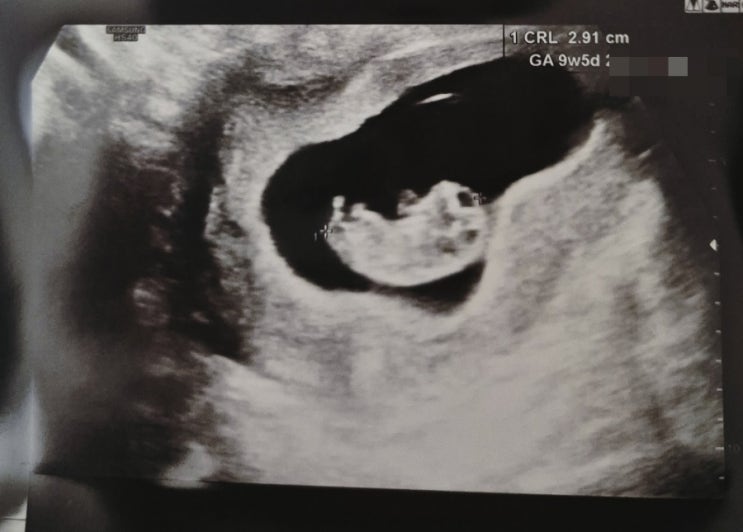

임신 7주차 10주차 강동고은빛 여성병원 산부인과 산전검사 젤리곰 하리보 초음파 심장소리

안녕하세요! 오늘은 임신 7주차 10주차 강동고은빛 여성병원 산부인과 산전검사 임신초기검사 하리보 젤리...